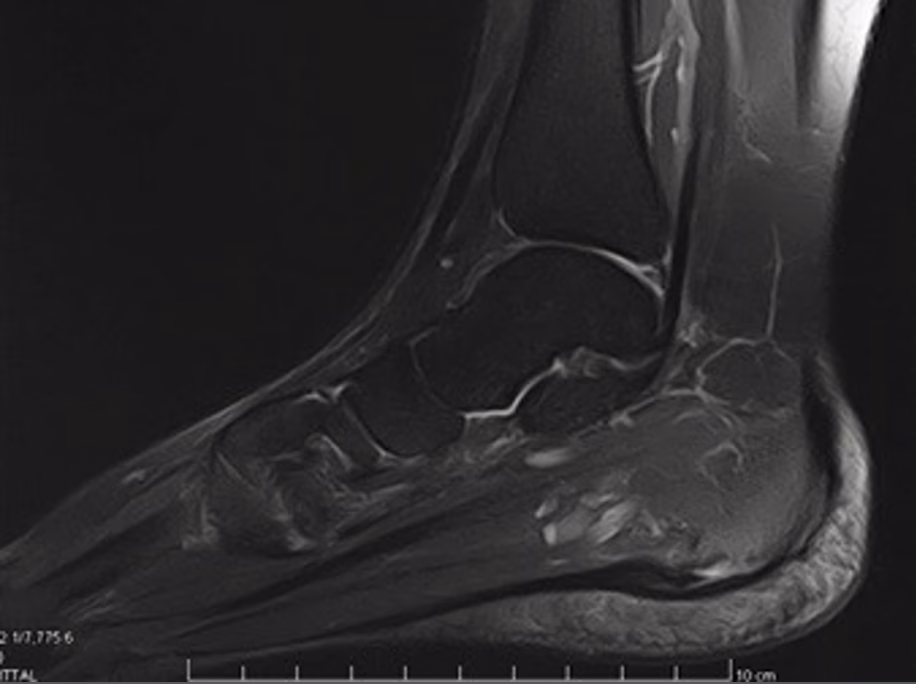

Assessment typically includes a detailed history and examination, and, when the diagnosis is unclear or the symptoms are complex, imaging such as ultrasound or MRI.